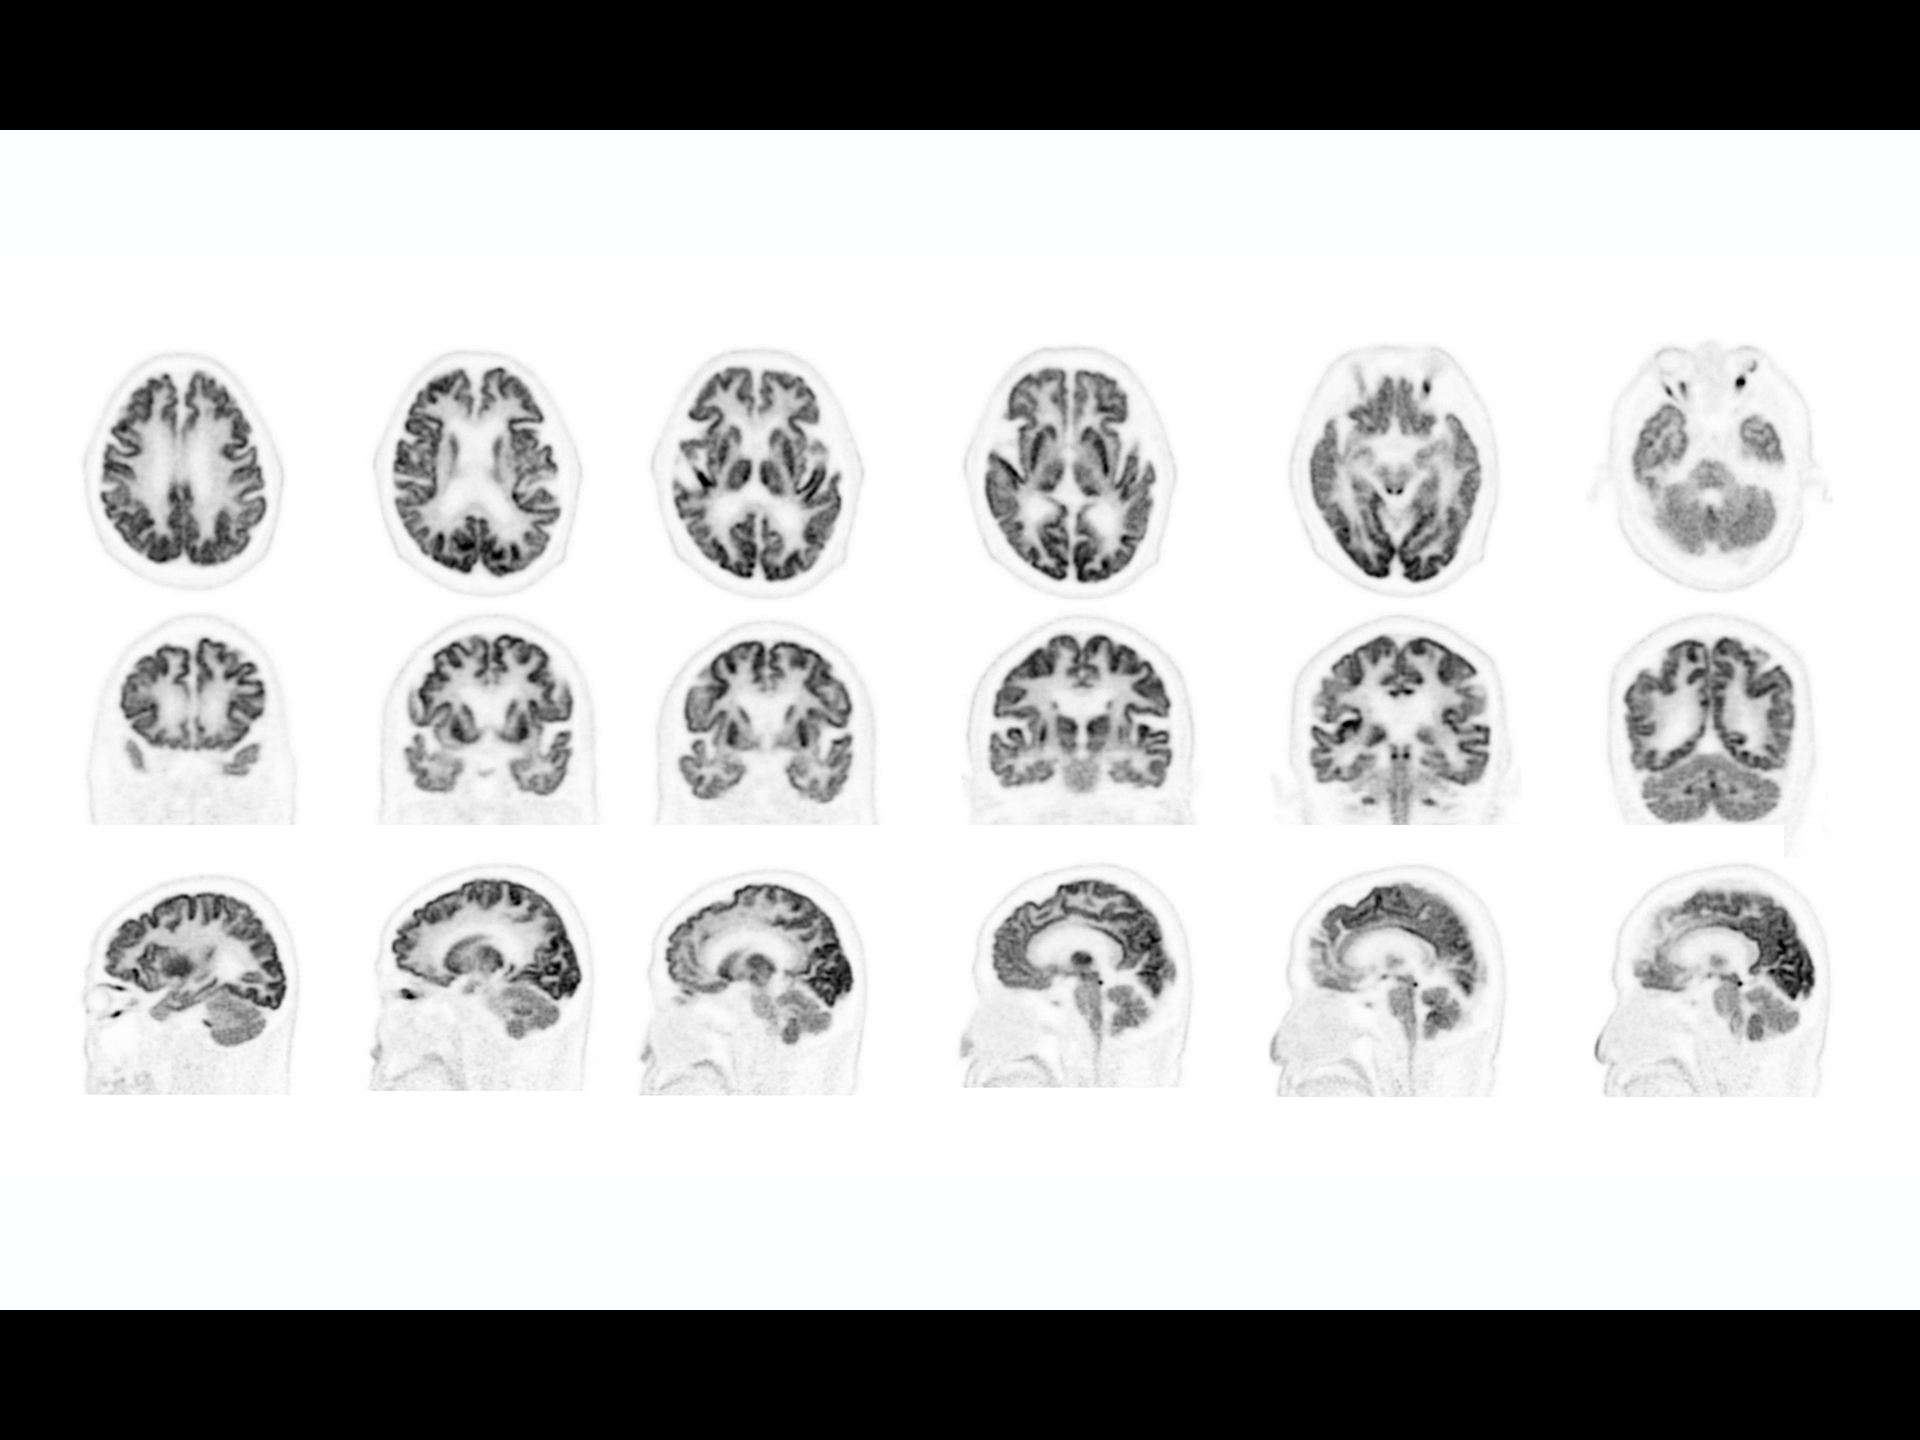

Exceptional NEMA spatial resolution delivered by the finest crystal size of 2.76 mm in the industry.

Leading TOF resolution that boosts small lesion detectability and clarity.